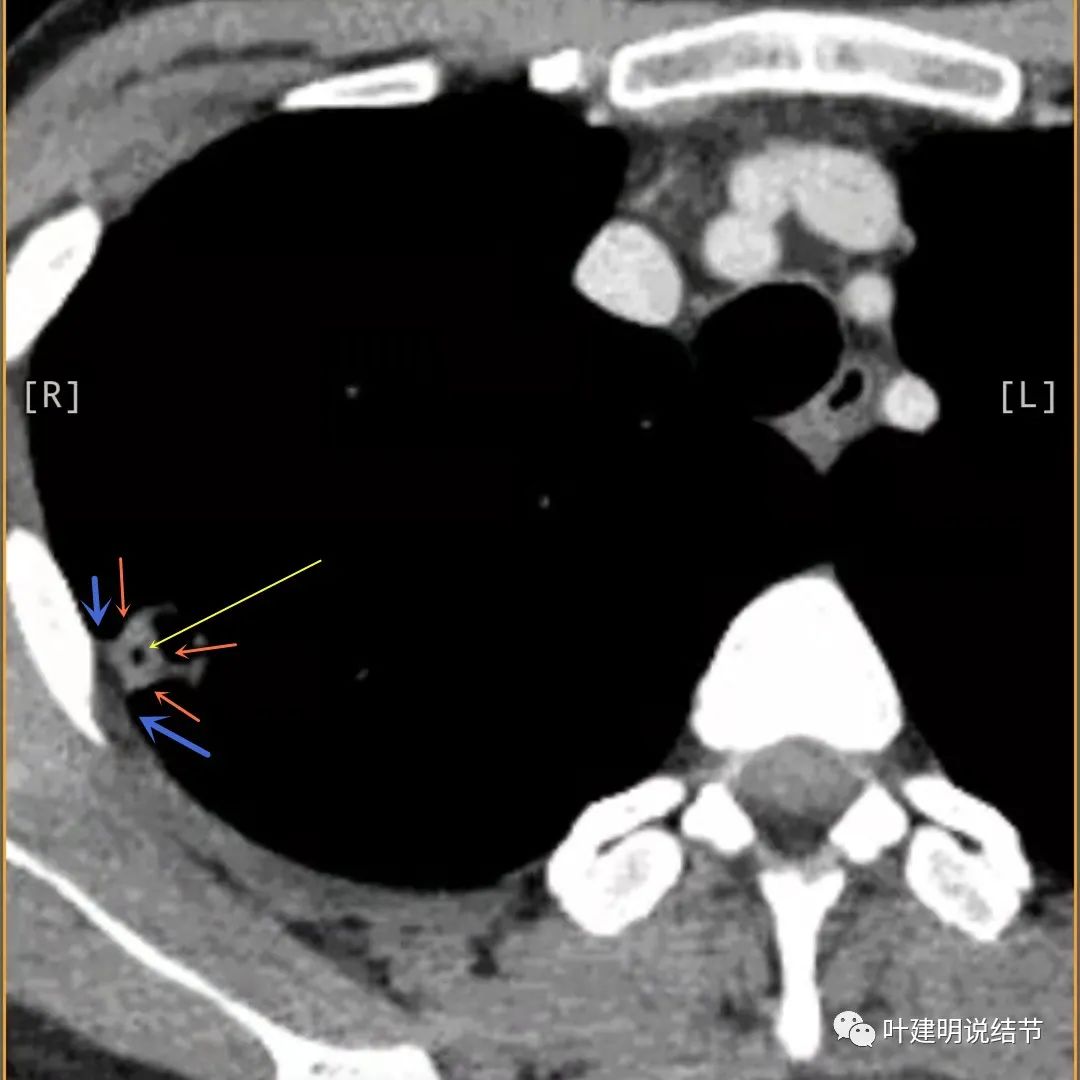

邻近胸膜有增厚(蓝色箭头),主病灶边界较清(红色箭头),实性部分密度过高(粉色箭头),旁边有磨玻璃影,散且模糊(砖色箭头)

邻近胸膜有增厚(蓝色箭头),主病灶实性部分密度过高(粉色箭头),旁边有磨玻璃影,散且模糊(砖色箭头)

邻近胸膜有增厚(蓝色箭头),主病灶实性部分密度过高(粉色箭头),旁边有磨玻璃影,散且模糊(砖色箭头),病灶有空腔(黄色箭头)